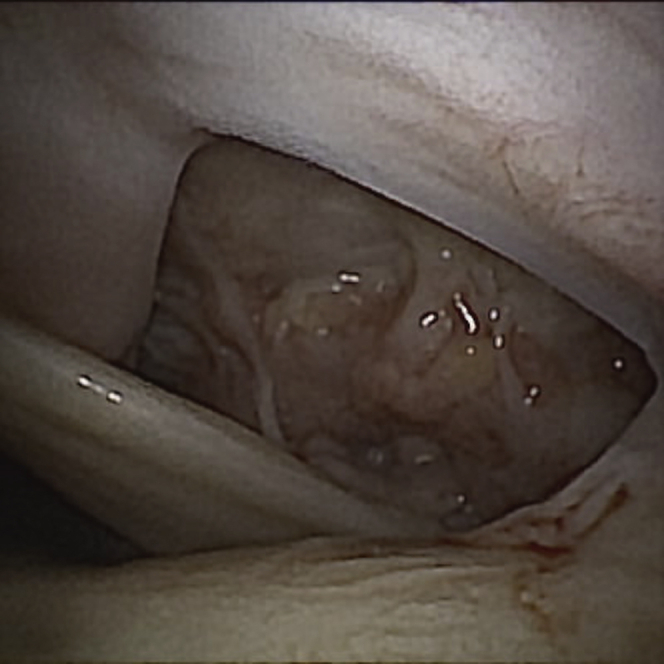

Fig 4.

Diagnostic nanoscope view from the glenohumeral joint of the right shoulder, showing rotator cuff tear and hourglass biceps.